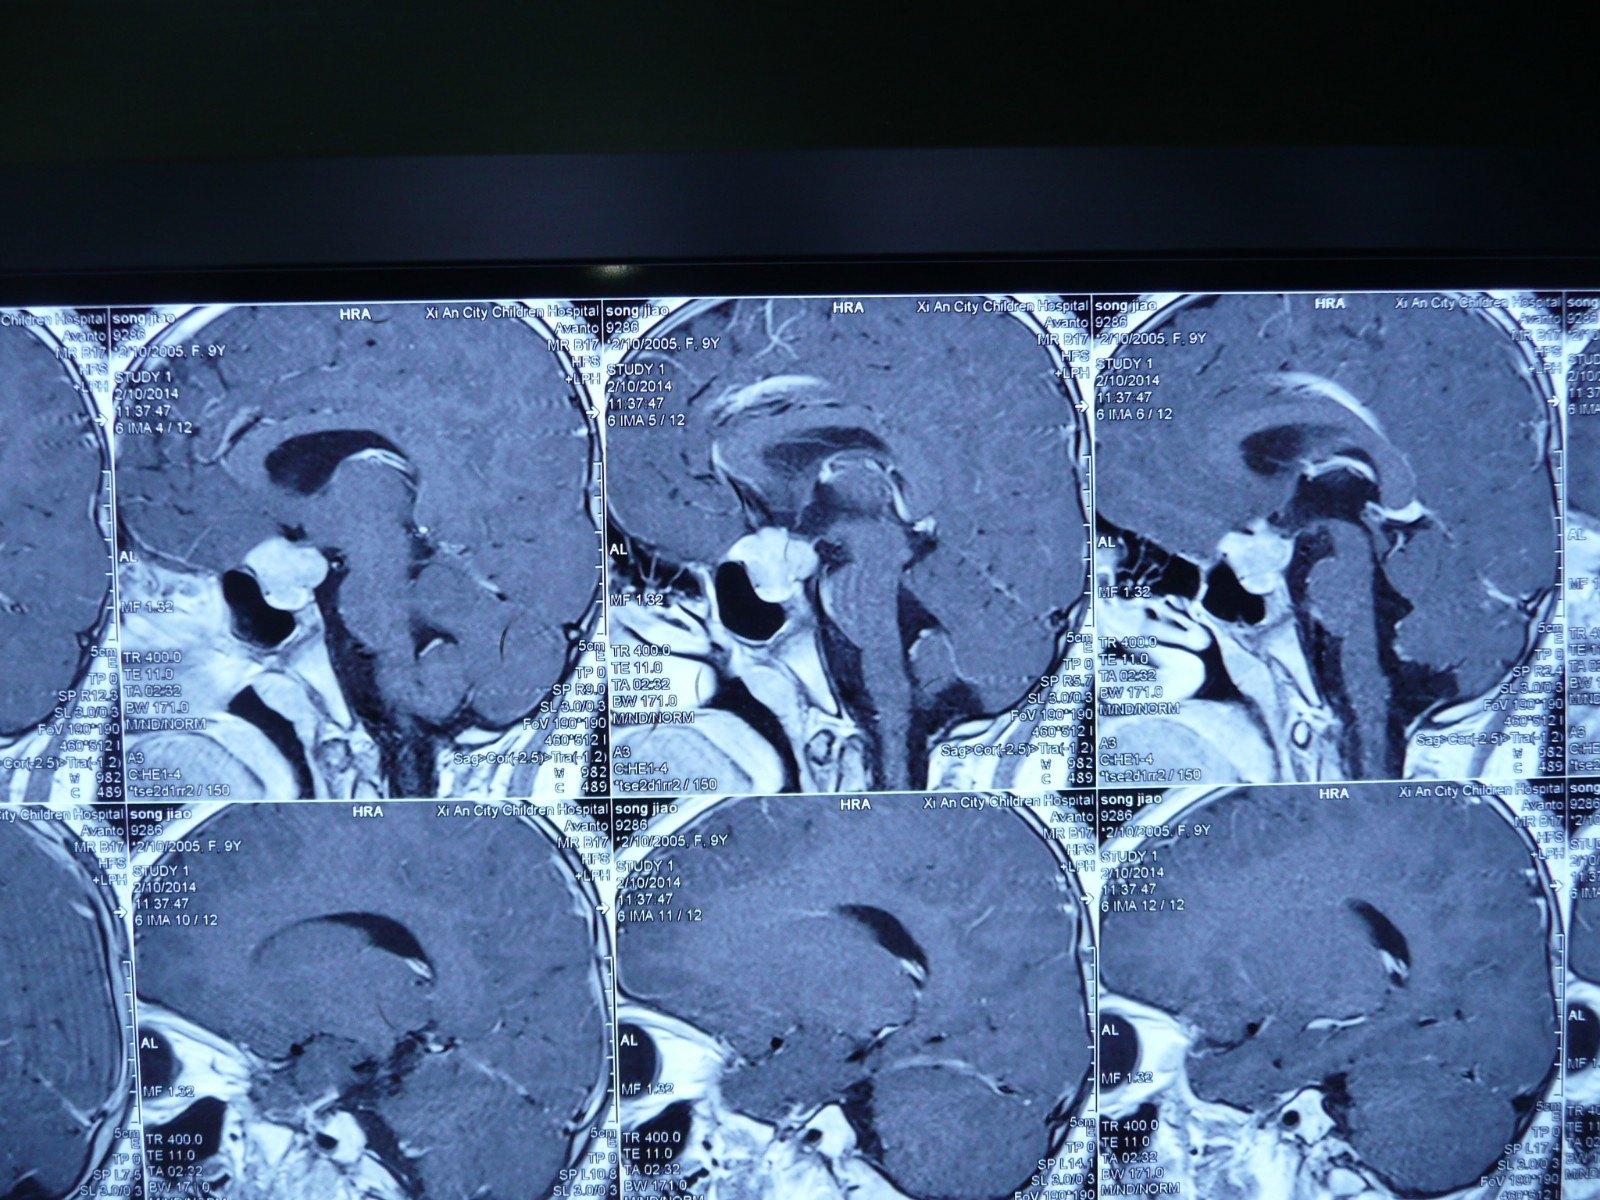

贺晓生教授儿童垂体腺瘤的诊断和手术案例

头颅ct:瘤体消失(图4,5)分析:儿童鞍区常见颅咽管瘤,垂体瘤相对少见